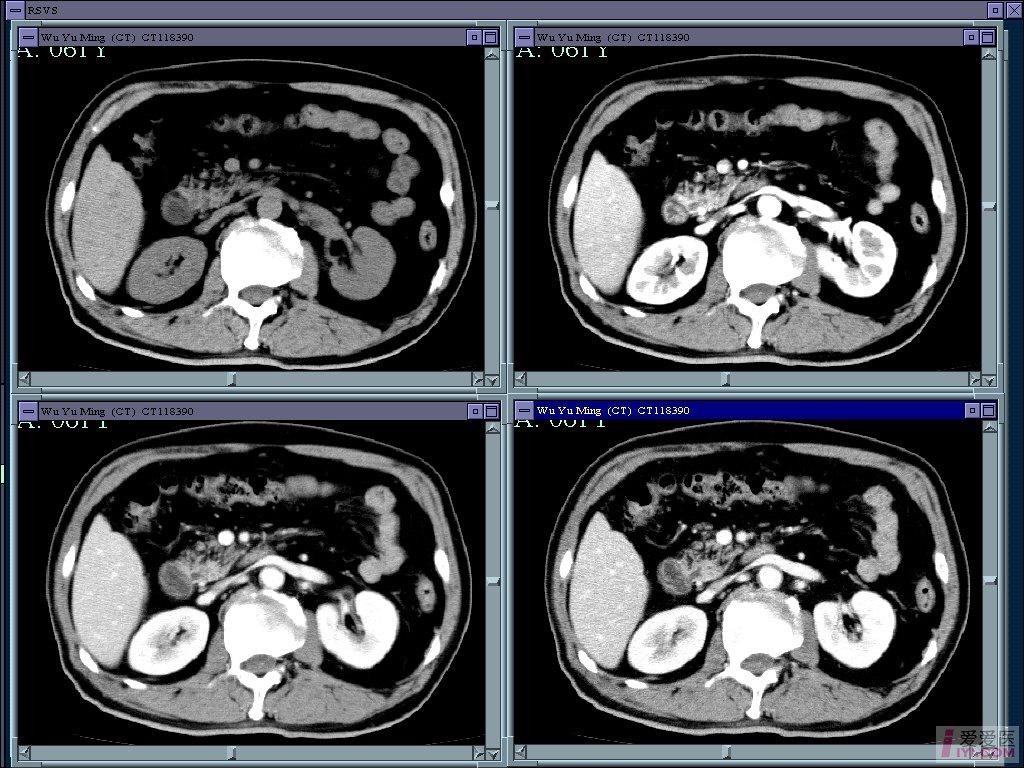

病例十二指肠旁疝1例ct影像表现